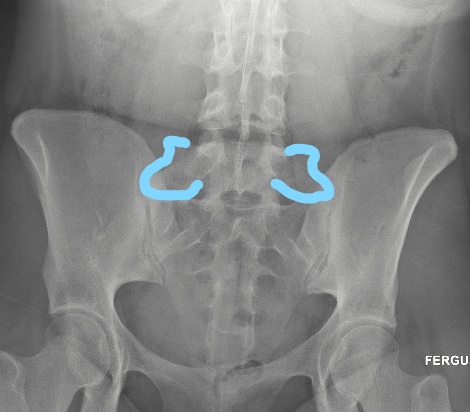

On the below radiograph of the pelvis, the enlarged

transverse processes are outlined in blue.